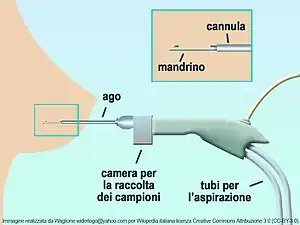

| Trocar |  |

Access instrument. Used to create an opening into a space without opening the abdominal cavity. A camera then inserted through one to view the inside of the space while instruments are inserted through the others to manipulate the organs. | |